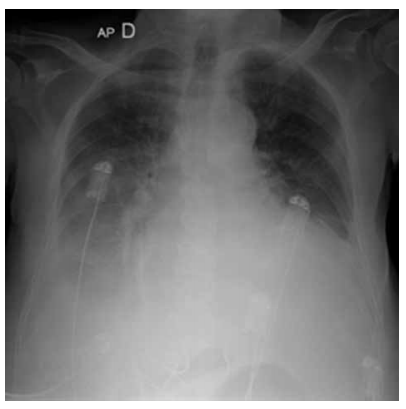

Homem, 76 anos, hipertenso e portador de miocardiopatia isquêmica, queixa-se de mal-estar, dispneia em repouso, dispneia paroxística noturna e, na última semana, ortopneia. Medicamentos em uso: captopril 25 mg; a cada 8 horas; furosemida 40 mg; espironolactona 50 mg; aspirina 100 mg e sinvastatina 20 mg. Exame físico: paciente lúcido e orientado no tempo e no espaço, presença de edema em membros inferiores 4+/4, extremidades frias, perfusão lentificada, pressão arterial = 90 x 50 mmHg, SpO2 = 89%, ausculta cardíaca com terceira bulha e ausculta pulmonar com estertores crepitantes nos dois terços inferiores de ambos os pulmões. Realizada radiografia de tórax, que está ilustrada a seguir.